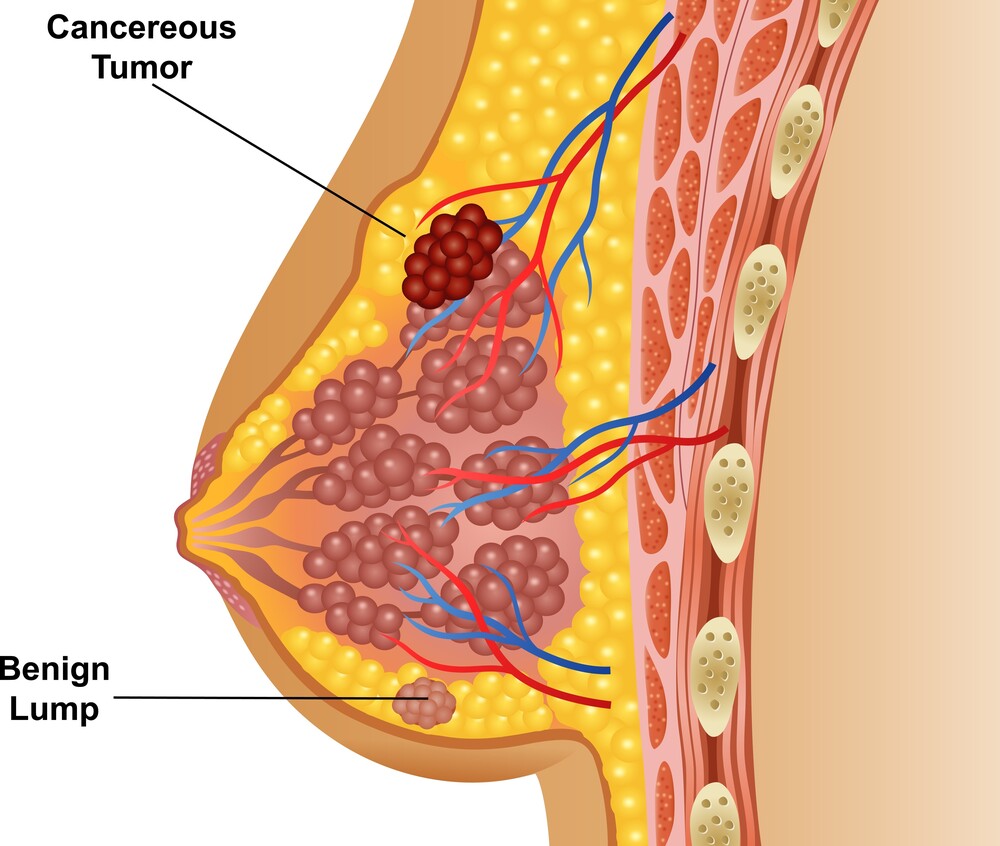

Lump or thickening

Lumps or thickened tissue can occur anywhere in the breast, including up to the collarbone and in the axilla. Breast lumps can present differently in different patients, e.g. they may be hard, soft, painless, painful, fixated, mobile, near the skin’s surface or deep in the breast tissue. A lump can also present as a thickened area of breast tissue that feels different from the rest of the breast.

Dimples and puckering

These can appear anywhere on the breast, including on the underside, and may be caused by a tumour pulling the overlying skin inwards.